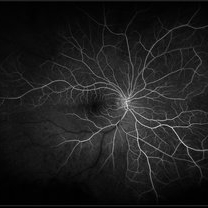

BRAO (3 files)

BRAO (3 files)

BRAO (3 files)

BRAO (3 files)